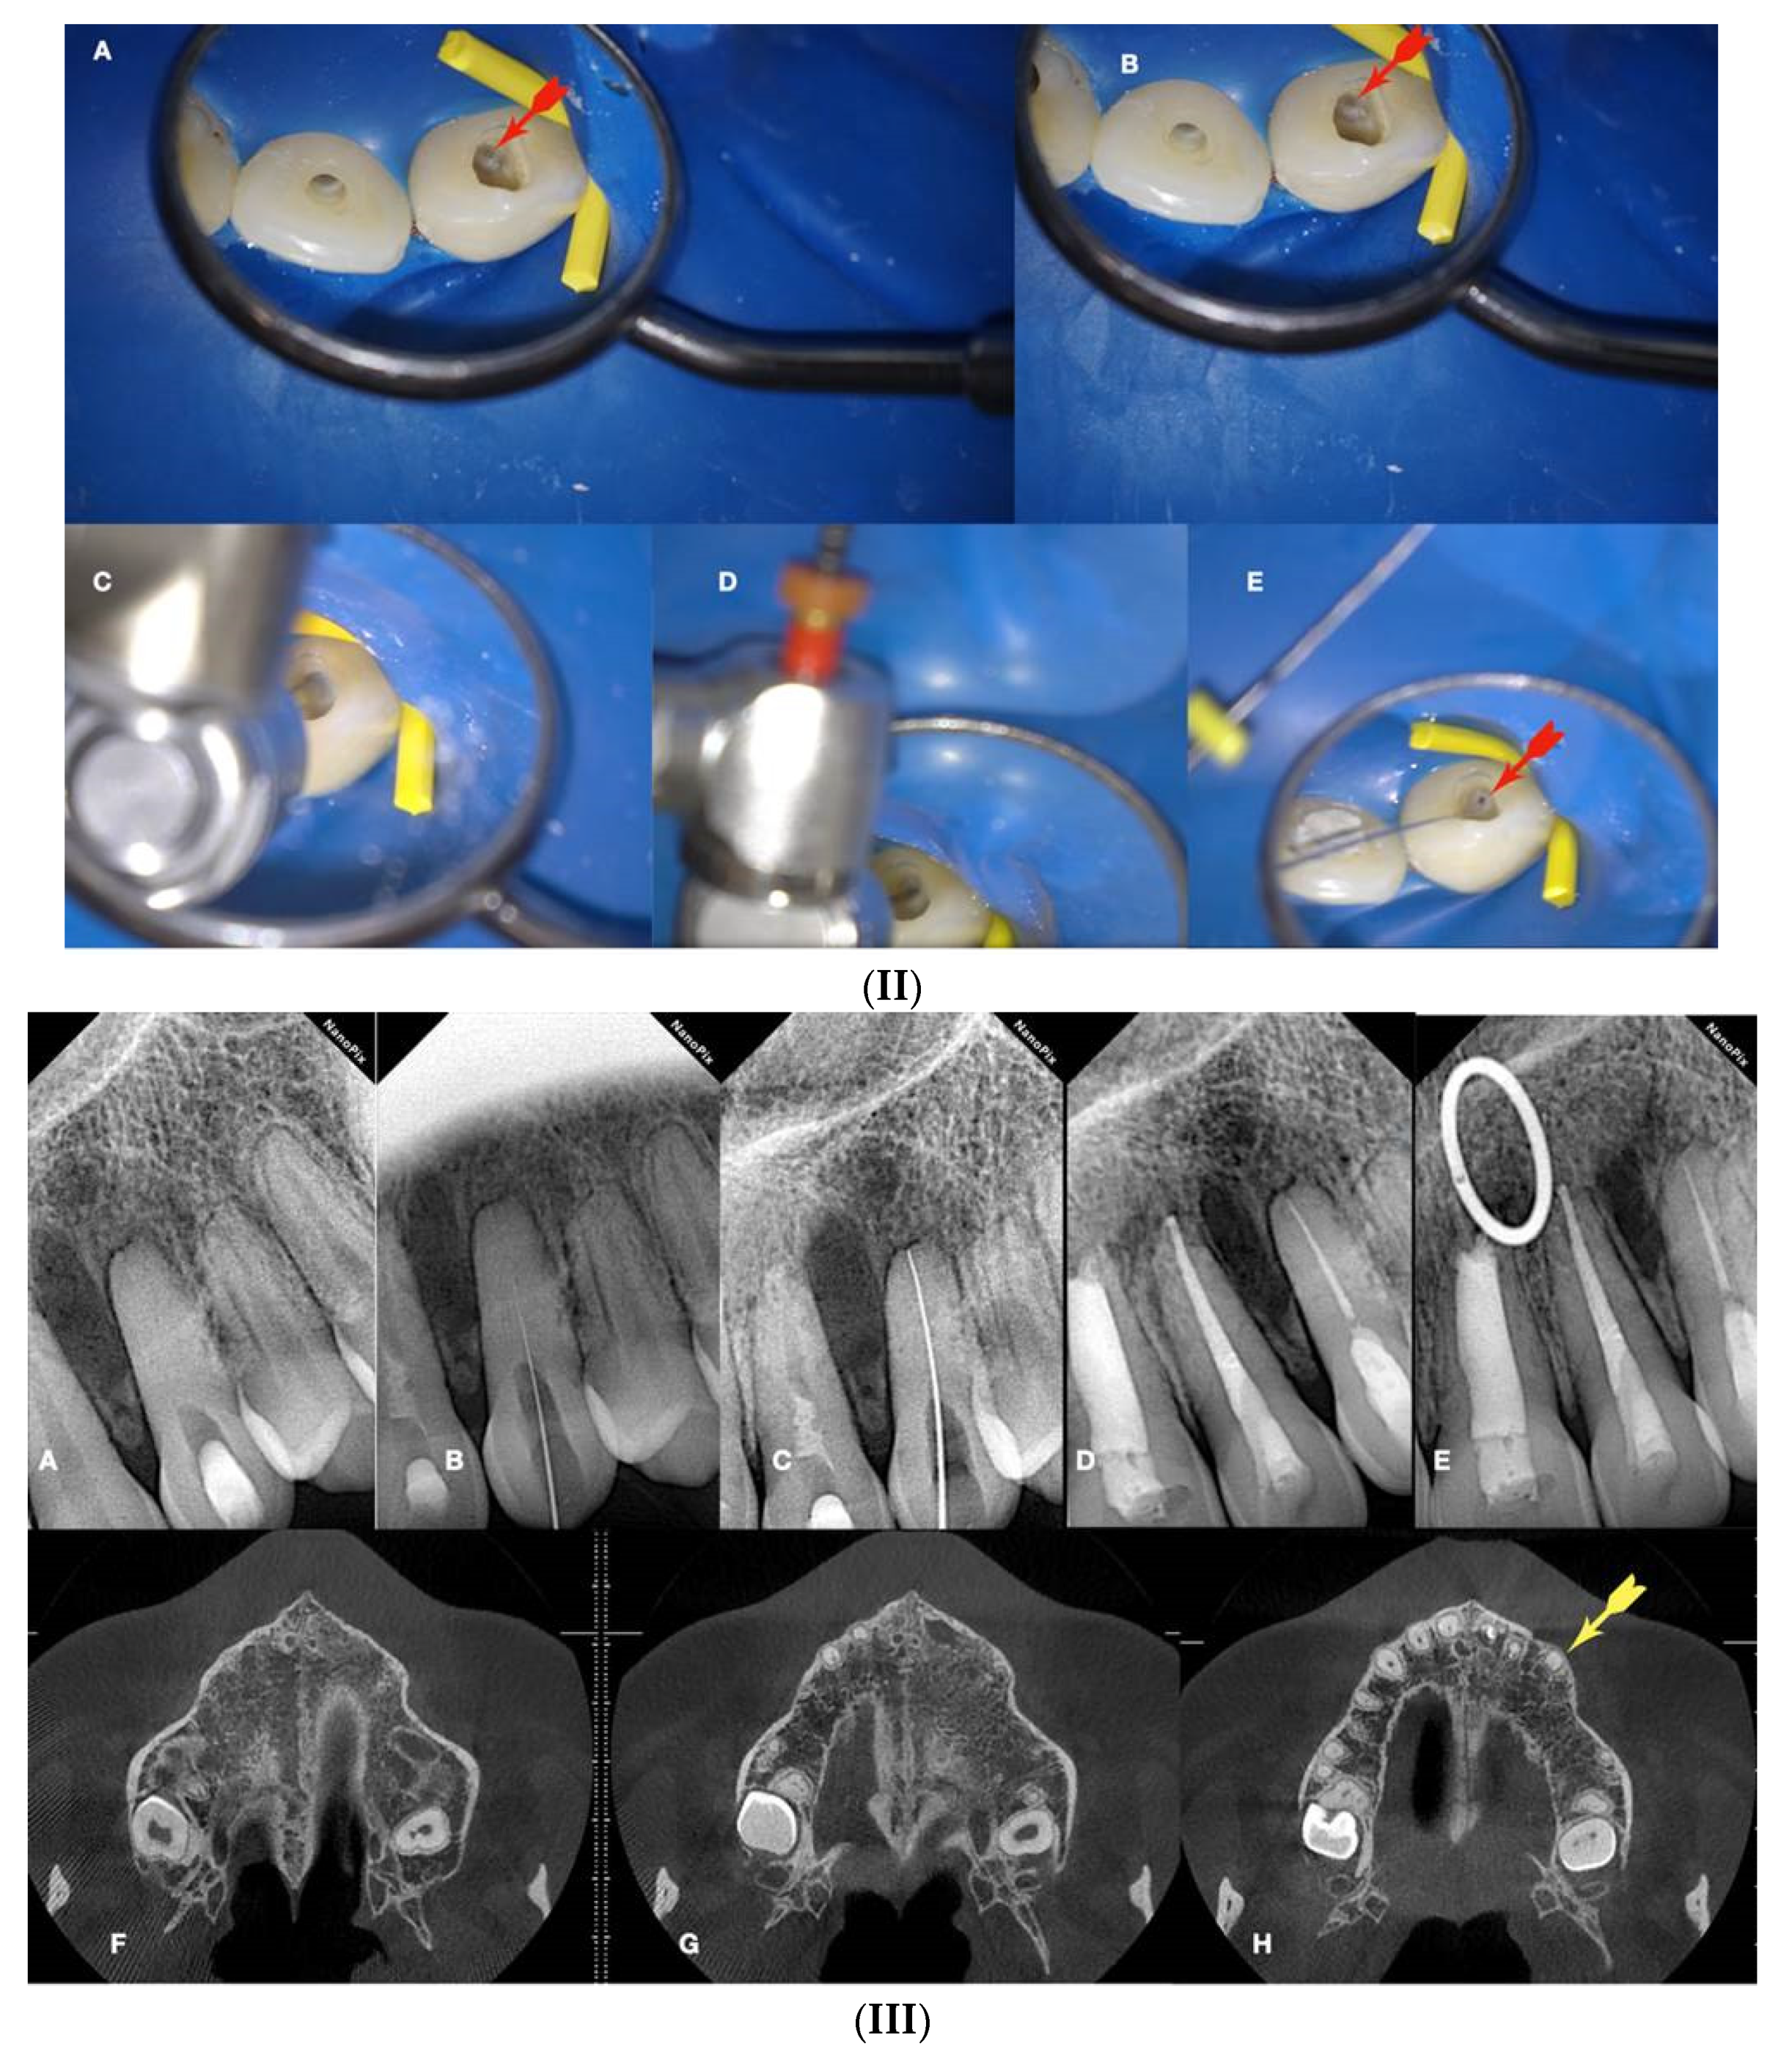

Figure 9.

a. Radiographic image of an extracted partially calcified maxillary premolar, b, magnified view at the level of the axial cut (grey area in a), c, & d. creation of initial access dimple in the white spot indicating the calcified orifice, e. continuous chelation of the cut dentinal surface, f & g. initial unsuccessful attempt to negotiate the calcified canal orifices with D- finder files iso 08, h. Fitting of the tip of an EDM file (Hyflex EDM -one file, Coltene) in the dimple without activation, j & i. On-spot buckling activation test (BAT) negotiation of the EDM files, k. negotiation of the 08 d-finders inside the calcified canals after the BAT negotiation technique removed coronal calcified canal obstructions, l. radiographic verification of calcified canal negotiation.